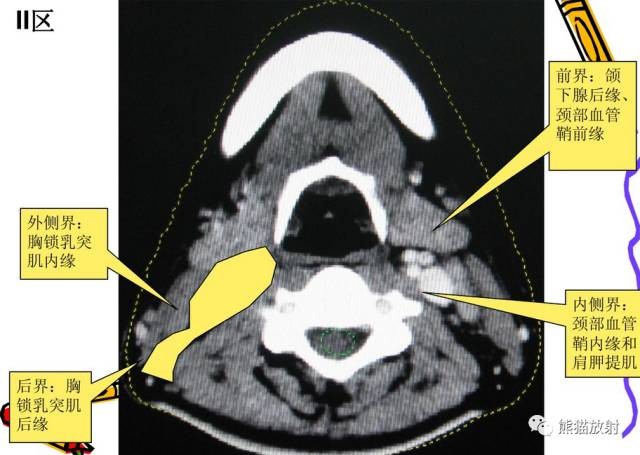

II区:颈内静脉链上组

舌骨上水平CT增强图像

横白线在两侧颌下腺后缘。

线以前为I区淋巴结,线后为II区淋巴结。在颈内静脉附近为IIA区,颈内静脉后面不接近静脉的淋巴结为IIB区。